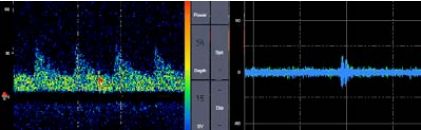

脳梗塞急性期から、MRIと 頸動脈エコーと経頭蓋のHITS(high intensity thrombotic signals)で

再発作をコントール

頸動脈病変の評価

- 左内頚動脈に低輝度プラークとNASCET法80%の狭窄性病変

- 経頭蓋超音波検査にて左MCAで30分間にHITSが9個検出された。

- 左内頚動脈の硬化病変を原因とするアテローム血栓性脳梗塞

- HITSを指標として抗血小板薬の治療効果が検証